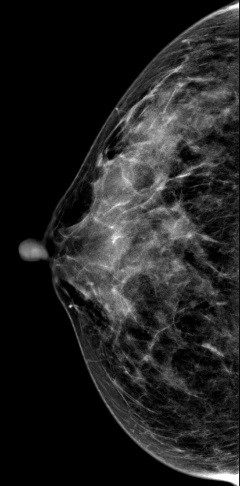

病史:患者43岁,发现右乳包块2周。

V-preview图像:

常规2D图像MLO位上象限见一团块状影,在CC位上并没有发现可疑异常密度影,在V-Preview图像和tomo图像上我们可以清楚发现病变边界不清见长短不一毛刺,呈星芒样改变。

右乳上方略偏外局限致密影BI-RADS 4B 。

在TOMO图像上对星芒样病灶周边情况显示明显优于2D图像,最后病理证实右乳浸润性导管癌。